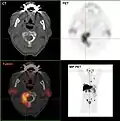

Les métastases osseuses de divers cancers peuvent être très bien visualisées par TEP/scanner. Le procédé est plus sensible que la TEMP et notablement plus que la scintigraphie, cependant, plus sophistiquée, et donc plus onéreuse. Selon de type de tumeur primitive, on utilise divers traceurs, mais le plus souvent le Fluorodésoxyglucose (18F) et le fluorure de sodium NaF (18F), et aussi pour le cancer de la prostate la choline (18F). L'activité métabolique de la tumeur est le plus souvent bien visible avec le FDG, et la réaction de l'os à la métastase avec le NaF[124].

- TEP/scanner à la choline 18F

Métastases ostéolytiques dans la deuxième vertèbre du cou (Axis) d'un cancer de la prostate.

Métastase ostéocondensante d'un cancer de la prostate dans la hanche

Scanner d'une métastase d'un cancer de la prostate à gauche dans le pubis (à dr. sur l'image)

TEP de la même métastase au pubis

Image composite scanner/TEP de la même métastase